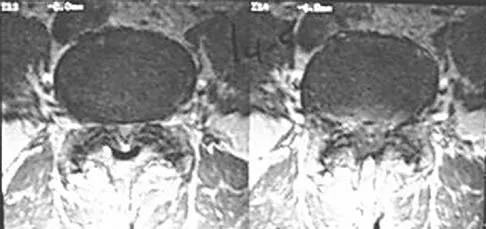

Figure 33 shows the MRI scan of a 55-year-old woman who has had a 6-week history of back and leg pain. Which of the following clinical scenarios is most consistent with the MRI scan findings at L4-L5?

The MRI scan reveals a L4-L5 foraminal disk herniation originating from the L4-5 disk space that has migrated up into the foramen, compressing the left L4 nerve root. There is normal distribution of the roots in the cerebrospinal fluid, excluding arachnoiditis as a diagnosis, and disk herniation in this location would not result in cauda equina syndrome or myelopathy.